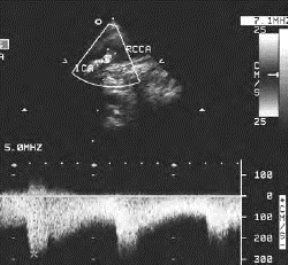

1.26.3三、正常血管

1.26.4四、动脉闭塞性疾病